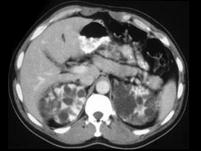

女,35岁,请根据CT图像,选择最可能作出诊断 ( )A、多囊肾B、单纯性肾囊肿C、多发性肾囊肿D、肾脓肿E、囊性肾癌

问题 女,35岁,请根据CT图像,选择最可能作出诊断 ( )

选项 A、多囊肾 B、单纯性肾囊肿 C、多发性肾囊肿 D、肾脓肿 E、囊性肾癌

答案 A